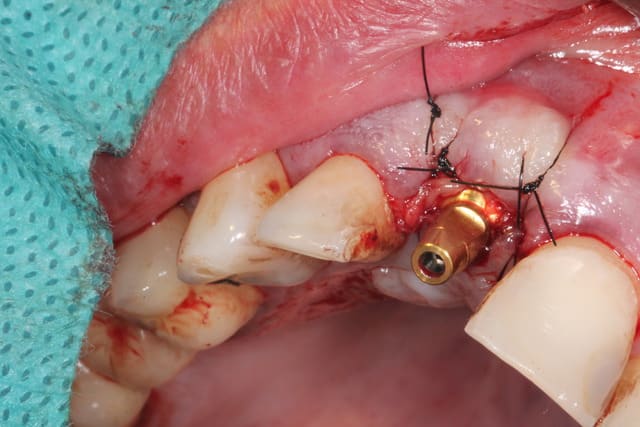

J'attendais d'avoir terminé le cas pour vous le présenter.

Il s'agit d'une EIIMCI avec comblement du gap.

J'ai utilisé un pilier plein que je n'ai pas déposé depuis la chirurgie.

Aurait-on obtenu le même résultat avec un pilier transvissé?